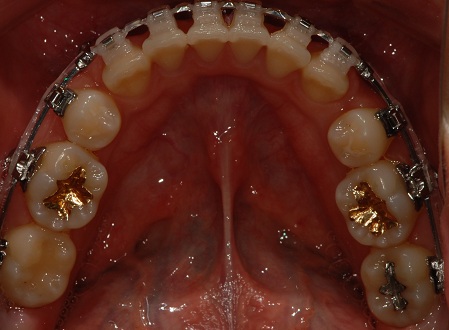

상악 사진